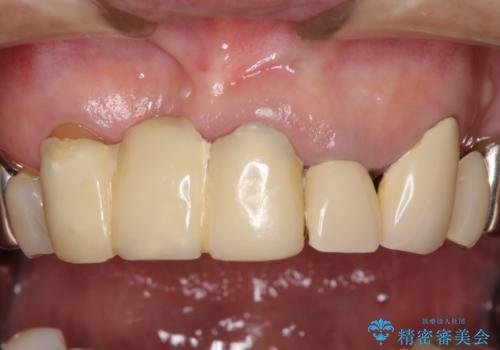

着色が著しい前歯のブリッジをオールセラミックできれいに

- 保険診療の前歯のブリッジが、形態も色も不自然で気になるとのことで来院された患者様です。

神経の抜かれている土台の歯は根管治療を行った上で、オールセラミックブリッジにより補綴することとしました。